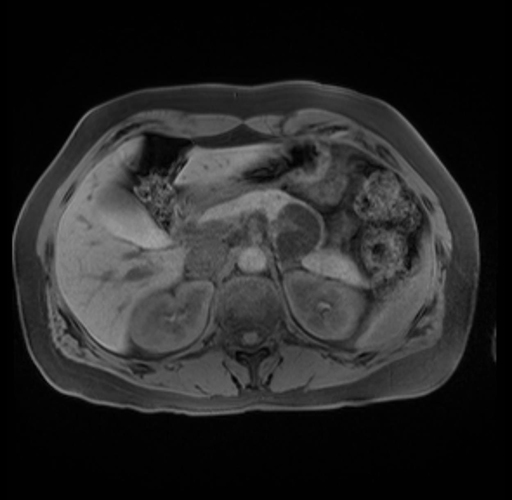

Imaging Analysis

Look through the patient's CT scan to identify any areas of concern for the necessary procedure.

Based on your CT findings, which issue(s) are present and would give reason for "planned slowing down moment(s)" in this case?